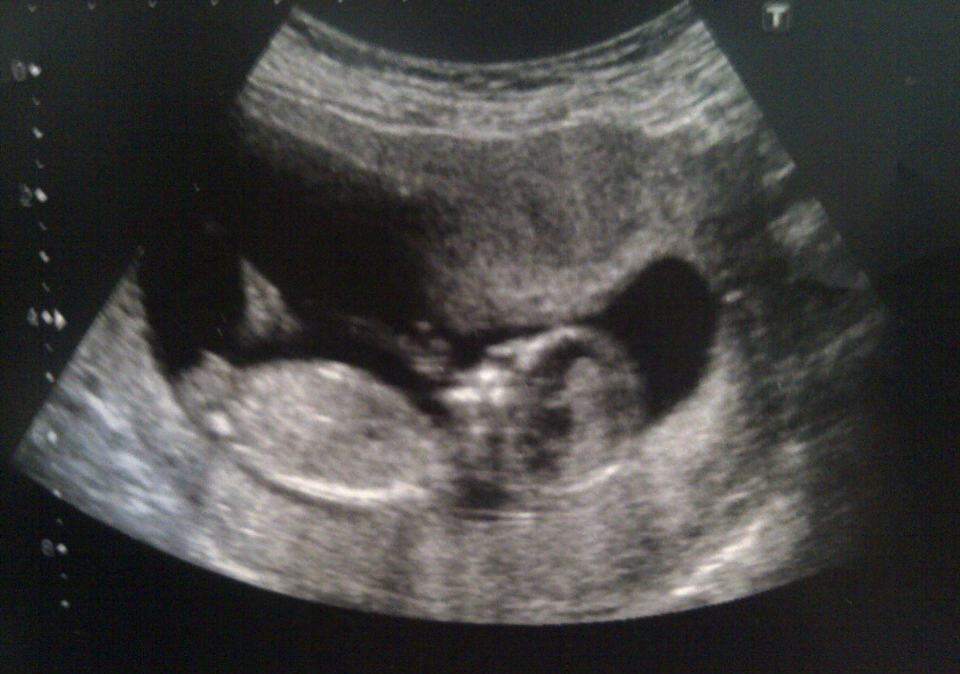

I would appreciate it if you could give your opinions on whether you think bubs is a boy or girl. The photo is from 13 wks 3 days. I am 17 weeks now so will post the result at my 20 week scan.